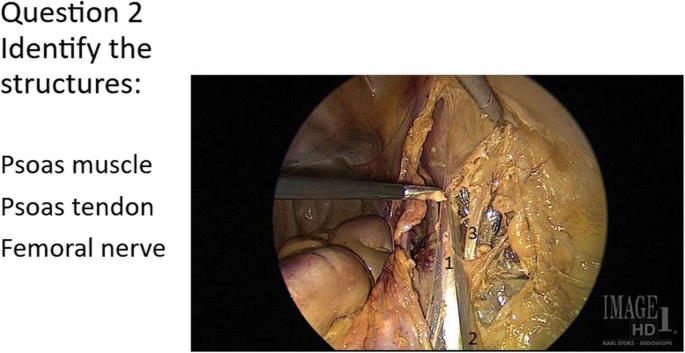

The identical Precourse and Postcourse Anatomy Surveys consisted of 12 images in which participants were asked to match structures on printed photograms from cadaveric laparoscopic dissections with answer choices, with 50 structures for a maximum score of 50 points. The tests were picture-based and the only English words used were anatomic terms. A representative sample question is included (Fig. 2). Given that all South American participants had registered for the course knowing it would be in English and thus self-selected for English proficiency, and given that the test was picture-based, we did not expect language to present a barrier to understanding the test.